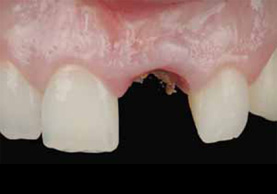

インプラント治療は、歯が抜けてしまった部分に人工歯根を埋入し人工歯をかぶせる治療法です。

インプラント本体は手術によって顎骨に埋め込みますが、顎の骨としっかりと結合・固定されるため、健康な自分の歯のようにしっかりと噛むことができるように機能性が回復します。

インプラント治療は、失った歯が1本から数本のケース、全歯が無く総入れ歯が合わないようなケースなどに対応しております。